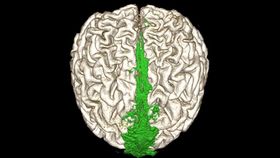

MRI showing the dorsal flow of the brain’s waste clearance system (shown in green).

Using this method, the authors scanned the brains of 81 epilepsy patients, revealing the presence of lymphatic structures running parallel to both the venous sinuses and the cranial nerve. These vessels direct the flow of waste products out of the skull, connecting to lymph nodes in the neck.

For a new study in the journal Nature Communications, researchers developed a safe, non-invasive MRI protocol that bypasses the need for toxic contrast agents. Instead, their technique produces images based on the natural contrast gradient that exists between the protein-rich contents of lymphatic vessels and the more diluted CSF.

“This is the first report to show the complete human brain lymphatic system architecture in living humans,” explained study author Onder Albayram in a statement.